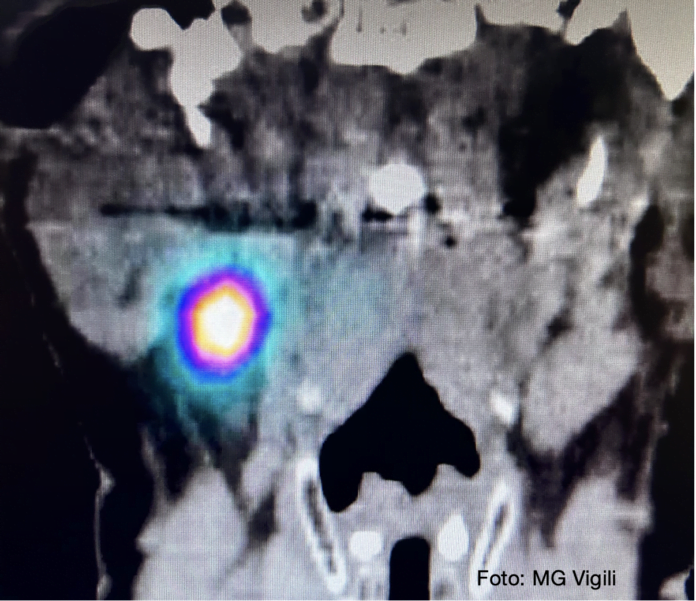

Linfonodo Sentinella nei T del cavo orale: fattori predittivi lo sviluppo di metastasi nei Linfonodi non Sentinella. Uno studio giapponese ha valutato nei Carcinomi squamosi del cavo orale piccoli sottoposti a biopsia del linfonodo sentinella positivo quali possano essere i fattori predittivi di metastatizzazione negli altri linfonodi del collo (NSN).

Su 162 pazienti sottoposti alla procedura di SNB, 55 sono risultati positivi e sottoposti a svuotamento latero cervicale.

In 9 casi si è riscontrata positività metastatica anche ai NSNs (16%).

Età avanzata, diametro del SN positivo (media 33.6 mm) e numero di SN positivi erano i fattori prognostici sfavorevoli.

Valutando i dati, per gli autori dello studio, i casi con Isolated tumor cells (ITC (4) e con micrometastasi, definita come metastasi isolata con focus metastatico < 3mm, potrebbero non dover essere sottoposti a svuotamento latero cervicale evitando un ulteriore 33% di interventi ritenuti non necessari.

Nella mia esperienza sui dati pubblicati (Eur. Archi Otorhino laryngol. 2020) su 15 casi di SNB positivo, in 6 casi (40%) sono stati riscontrati linfonodi non sentinella metastatici nello svuotamento latero cervicale. Nessuno di essi aveva avuto micrometastasi singola o ITC nel Linfonodo sentinella positivo. Credo che le deduzioni dello studio giapponese siano giuste ma occorre un maggior numero di casi per confermarle e decidere una ulteriore riduzione degli svuotamenti